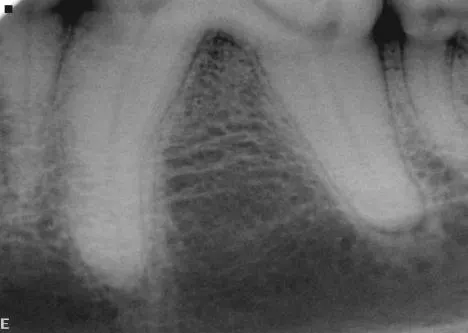

Dental images are best obtained with oral radiography techniques using dental film or a digital sensor and a dental x-ray machine. Locating the dental radiographic unit in the dental operatory makes it quick and easy to take dental radiographs. The film is placed intraorally in most instances to help eliminate overlap of structures. The tube head is manipulated into the correct position for taking the radiograph.

Skulls were used for these images. Dental images were obtained with a digital sensor; the traditional radiographs were taken using extraoral technique with a standard radiographic machine.

A dental radiograph shows the roots of a canine tooth with visible periodontal disease, including bone loss and changes in the surrounding alveolar bone structure. The image highlights the areas of concern for potential treatment and diagnosis.

A dental radiograph showing the roots of a canine tooth, highlighting the surrounding bone structure and periodontal tissues. The image reveals details of the root canal system and any potential signs of dental disease or abnormalities.